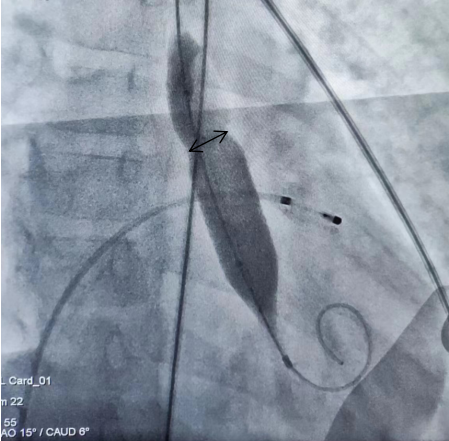

经过充分准备,今日手术如期进行。手术是在大腿的内侧的股动脉,穿刺建立约 2 mm 的通道,然后通过把导丝通过血管进入到心脏,对狭窄部分进行扩张。接下来再通过导管将封堵器送至动脉导管未闭合的区域进行封堵,不到一小时,手术顺利结束!

术后心脏彩超和心导管检查提示,术后主动脉瓣压差降至 20 mmHg 左右,手术非常成功。